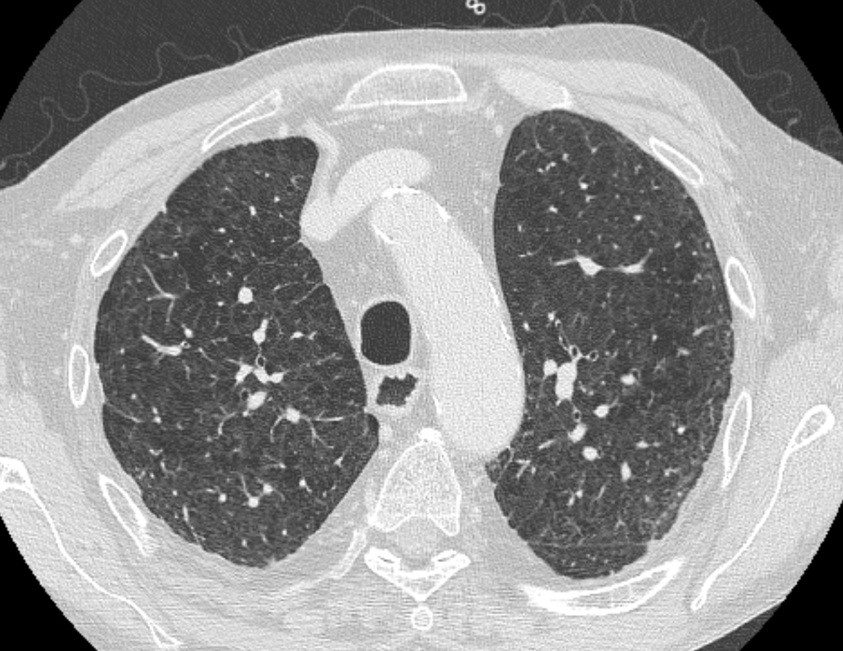

Emphysema is characterized by permanently enlarged airspaces distal to the terminal bronchiole, with destruction of alveolar walls. Emphysema is usually classified according to the part of the acinus predominantly affected. The Computed Tomography appearance of emphysema consists of focal areas or regions of low attenuation, usually without visible walls.